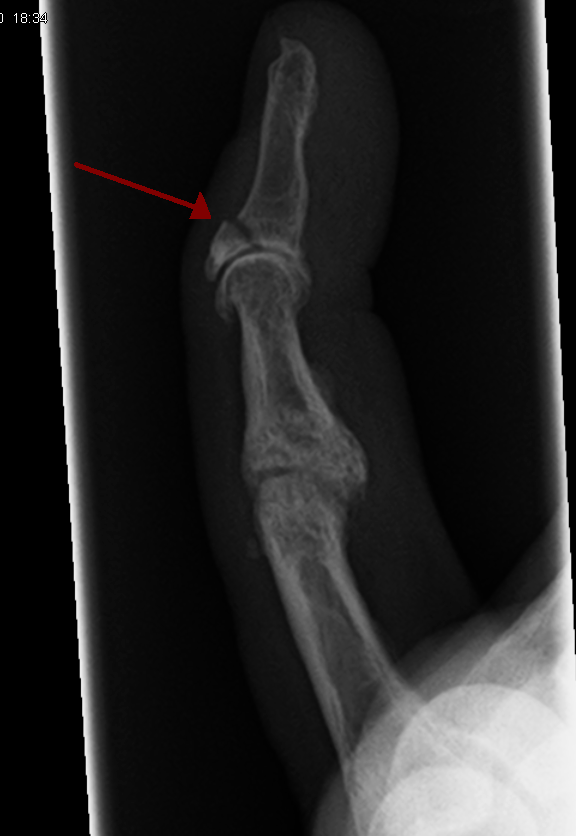

Corriere della Sera: Claudio Zorzi, il chirurgo che è già morto due volte: «Curai il ginocchio di Sofia Goggia e dopo 15 giorni vinse l’argento. Papa Francesco aveva un’artrosi ai piedi terribile»